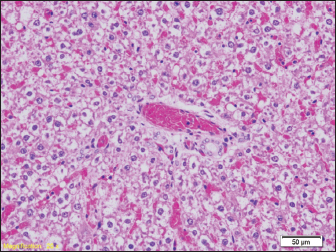

Signs of hydropic and vacuolar degeneration can be seen in the kidney samples of all groups of rats, and signs of acute tubular necrosis can be seen in one of the samples (group G2) (Figs. 7 and 8).

Fig. 8. Signs of hydropic and vacuolar degeneration in epithelial cells of renal tubules (HE, ×200). Brain tissue samples of all groups of rats show a lower or higher degree of edema (Fig. 9).

Signs of hydropic and vacuolar degeneration can be seen in the kidney samples of all groups of rats, and signs of acute tubular necrosis can be seen in one of the samples (group G1).

The pathohistological findings of the kidneys in all examined groups indicate hydropic and vacuolar degeneration of the epithelial cells of the renal tubules, and the pathohistological findings of the brain in all groups show signs of pericellular and perivascular edema. In our study, we did not find diatoms in the kidneys. Previous studies prove that the number of diatoms found may be lower than expected, as in liver samples. Since the middle of the last century, there have been certain disagreements among numerous authors about the reliability of diatom findings in internal organs such as the kidney, liver, or bone marrow. The reason for this is the high rate of occurrence of false positive findings (Timperman, 1969).

The results of the pathohistological examination of the kidneys in our study coincide with those of other authors. In previous studies, after drowning, signs of glomerular enlargement with hypercellular changes were found on the kidneys, signs of degeneration were present in the tubules, such as their uneven expansion and edema of the cells of the tubular walls, and in the interstitium, there were congested capillaries were present (Ibrahim et al., 2022). Seong et al. (2012) also reported signs of acute tubular necrosis after drowning (Seong et al., 2012).